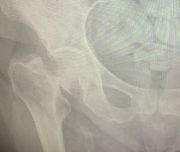

2. Comminuted extracapsular fracture of the left hip in a 69-year-old female.

Treatment: Nailing with a proximal femoral nail

I. Before surgery II. Post-surgery, x-ray showing the proximal part of the nail and the reduction of the fracture III. Post-surgery, x ray showing the distal part of the nail